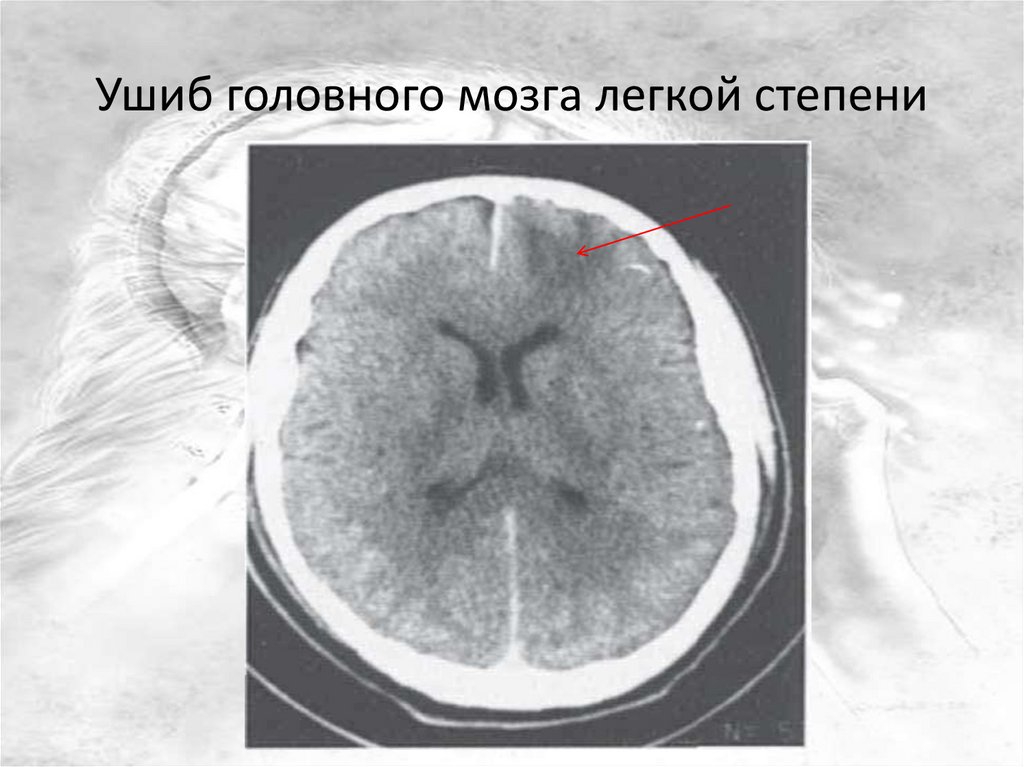

Ушиб головного мозга легкой степени

16.